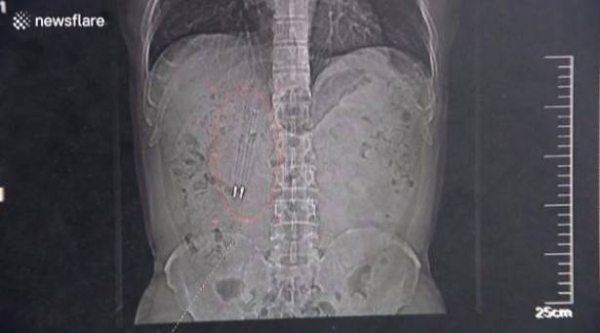

بعد 36 عاماً من ابتلاعهما .. استخراج قلمين من معدة رجل !

شاءت الأقدار أن يبتلع رجل صيني قلمي حبر نتيجة خسارته لرهان مع أصدقائه وهو في ريعان الشباب، حيث استقر القلمان في معدته وبقيا داخلها لأكثر من ثلاثة عقود.

قام الجراحون في أحد المستشفيات الصينية بإخراج قلمين من معدة رجل صيني يدعى وانغ، بعدما بقيا في جوفة لمدة 36 عاماً.

وقال الجراحون في مستشفى سوتشو، بمقاطعة جيانغسو الصينية، إن الرجل قال لهم إنه ابتلع القلمين قبل 36 عاماً بعد خسارته لرهان مع أصدقائه.

وقال وانغ للأطباء بأنه نسي ابتلاعه للأقلام طوال تلك الفترة حتى شباط الماضي، عندما أجرى صوراً شعاعية لجسمه.

من الجدير بالذكر بأن الأطباء نجحوا باستخراج الأقلام من جوف وانغ في الرابع والعشرين من نيسان الماضي، وهو يتمتع الآن بصحة جيدة، بحسب موقع "يو بي آي" الإلكتروني.